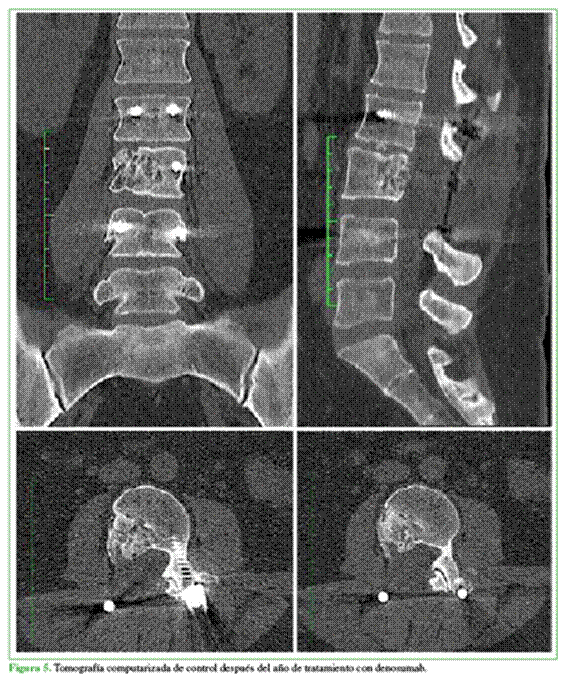

A los seis meses del procedimiento, la paciente no tiene síntomas. La tomografía computarizada y la resonancia magnética de control (Figura 4) muestran una imagen compatible con recidiva local del QOA. Después de consultar la bibliografía citada en este artículo, se discutió el nuevo tratamiento con las siguientes opciones: nueva vertebrectomía de L3, inyecciones intratumorales de corticoides y calcitonina, embolización del tumor, administración de denosumab. Se optó por el tratamiento con denosumab 120 mg, dosis inicial, cada tres meses, por dos años. A medio término se realizó un control tomográfico y se constató la remisión y la calcificación de la lesión (Figura 5).

En la actualidad, se discute el uso de denosumab para el tratamiento inicial de cuadros tumorales, pero sería una posibilidad terapéutica para tumores ubicados en áreas de difícil acceso para las técnicas quirúrgicas1,7,9 o inclusive para recidivas locales del QOA, pues se ha demostrado que permite la formación de hueso y la regresión tumoral,7-9 lo que se traduce en la disminución o remisión del cuadro clínico del paciente y la mejora radiológica del tumor. La eficacia máxima del tratamiento se logra a los seis meses.9 Si bien los resultados con denosumab son auspiciosos en la actualidad, como en nuestro caso, es preciso tener en cuenta que la eficacia de este fármaco se ha demostrado en estudios preliminares, y aun así los datos sobre la seguridad a largo plazo, las recurrencias y la duración óptima a largo plazo no son concluyentes; por lo tanto, se necesitan ensayos con más casos, estudios longitudinales y clínicos que avalen la duración del tratamiento y la consistencia del denosumab en el QOA.3,6,8-10

La administración de denosumab 120 mg como dosis inicial, y luego una dosis cada tres meses, hasta los dos años resultó beneficiosa para nuestra paciente con una recidiva local después de la embolización y la exéresis tu-moral, se logró la remisión total y la calcificación. El uso de este fármaco sigue siendo controvertido antes de una cirugía, ya que no se dispone de evidencia suficiente de pacientes tratados de esa manera.